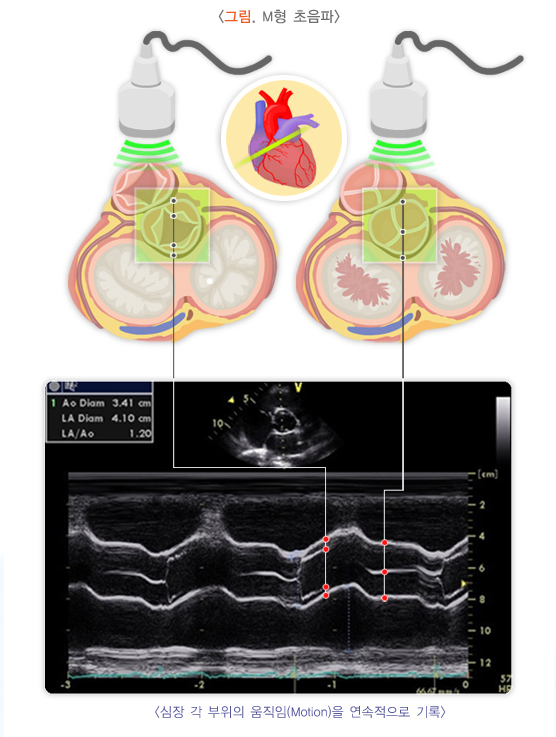

- 초음파 검사나 혈관 촬영을 통해 동맥의 상태를 주기적으로 확인하고, 혈류 상태를 점검해야 합니다.